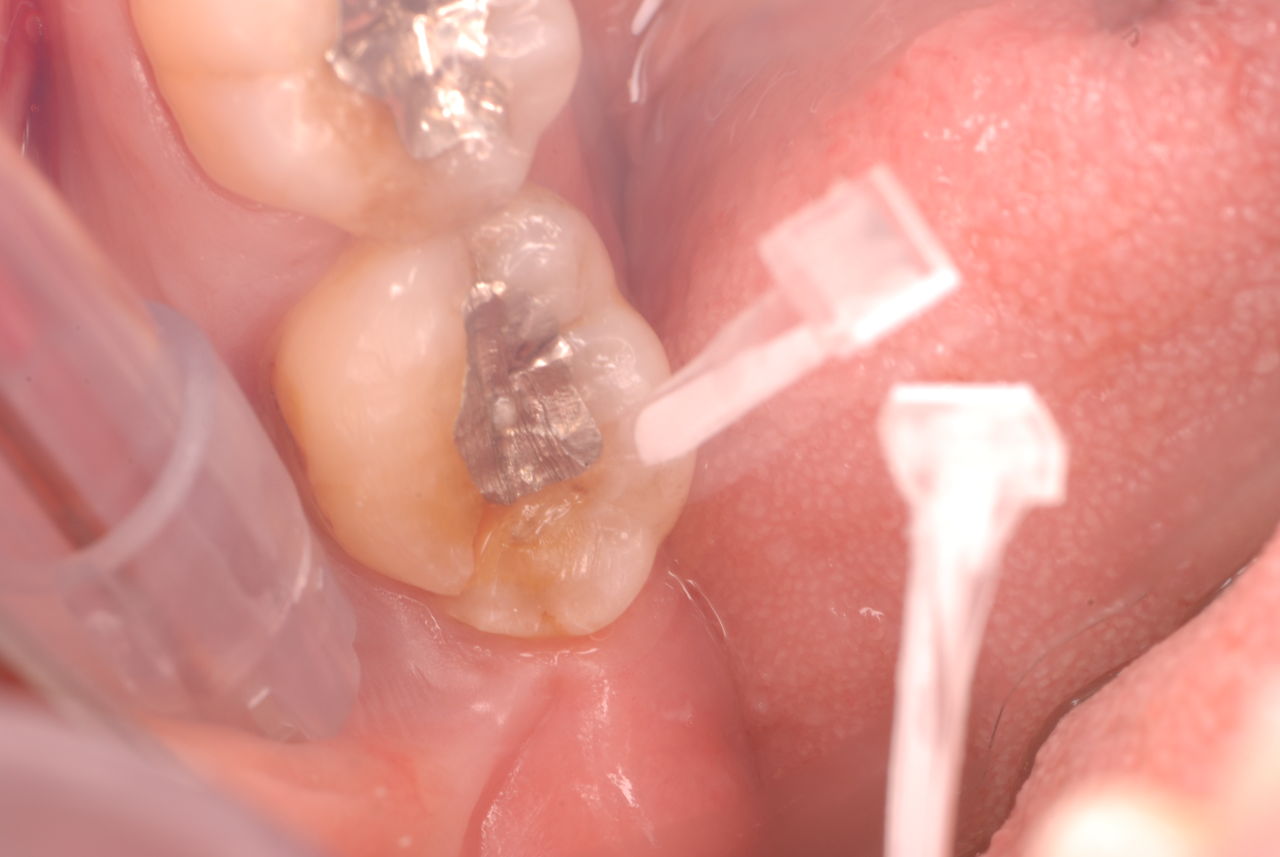

30代の男性の方です。

入れ歯を入れていました。歯科医院で歯を抜けず仕方なく入れ歯にしたとか。何とかならないものだったのか悔やまれました。

抜いた歯はありません。

一応差し歯にしましたが、歯茎の状態はよくはありません。

とりあえず希望を入れて差し歯にしたような感じです。